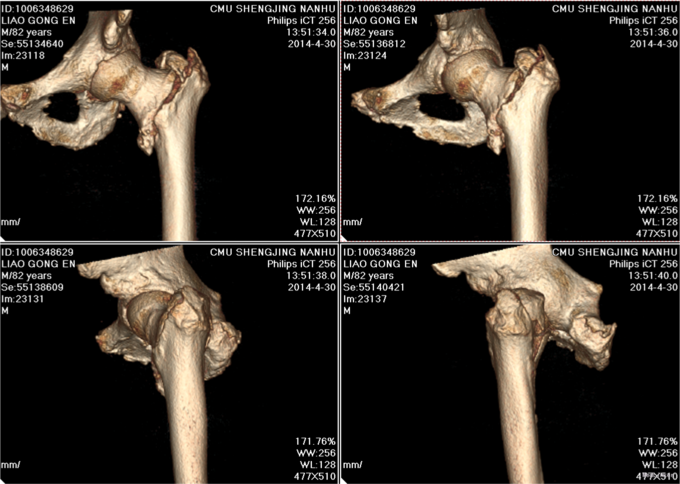

患者2014-04-27日上午9时摔倒后左髋部疼痛肿胀、活动受限,不能站立行走,急来中国医科大学附属盛京医院急诊科,急诊予以行辅助检查,左下肢DR提示:左股骨粗隆间骨折,现患者为求进一步诊治,以“左股骨粗隆间骨折”为诊断收入我科。患者自受伤以来一般状态可,无发热,无头晕、呕吐,无胸闷、心悸呼吸困难,无腹痛、腹泻,饮食可,睡眠可,二便正常。

左髋部未见明显肿胀及瘀斑,活动度减低,活动因疼痛受限,左髋部压痛阳性,叩击痛阳性,左下肢缩短畸形,缩短1cm,外旋80°。左膝及左踝关节活动无明显异常。双侧足背动脉搏动有力,肢体末梢血运良好,皮温正常。远端足趾感觉运动正常,